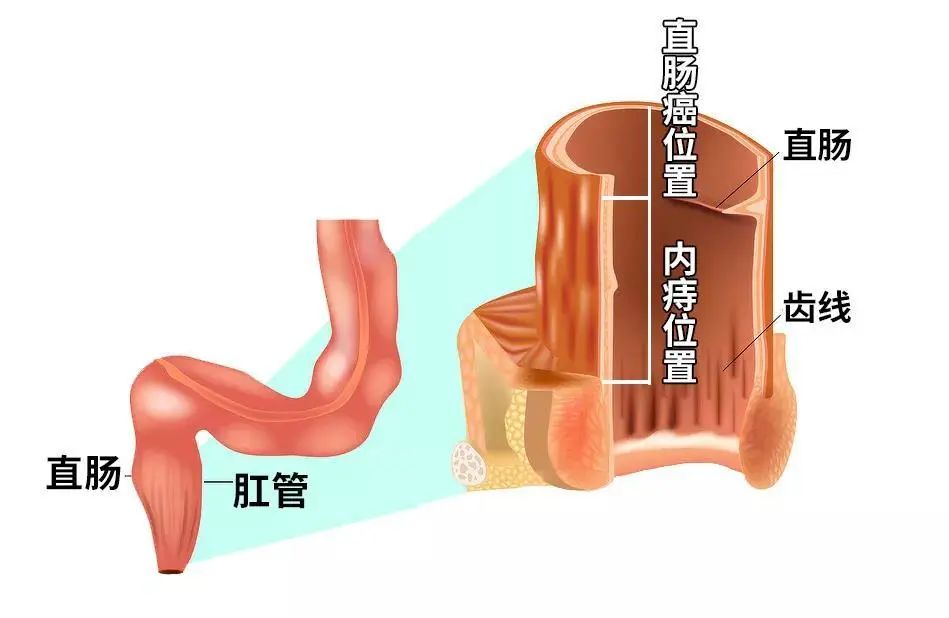

“内放疗”是一种放射性粒子植入术。医生利用现代影像学技术将具有放射性核素的粒子直接插植到肿瘤病灶内或肿瘤周围,放射性粒子通过持续释放射线对肿瘤细胞进行杀伤。“内放疗”属于高度适形放疗的一种,目前国内所应用的放射性粒子主要指碘125粒子。8Wz帝国网站管理系统

我“身高”4.5mm,“腰围”0.8 mm,肚子里装着吸附碘125粒子的银棒,外壳为0.05 mm厚的钛金属。我是“0-0-7”哦,可以24小时持续工作(释放能量)。另外我射线射程短(组织间有效射程直径只有1.7cm),大部分射线能量均被瘤体及组织所吸收,所以大家不用害怕我,无须特殊防护。

碘125粒子发出γ射线,该射线可以破坏肿瘤细胞核的DNA双链,导致DNA分子链的单链断裂或双键断裂,使肿瘤细胞失去繁殖能力; 射线还可以使机体内的水分子电离,产生自由基,该自由基与生物大分子相互作用,引起组织细胞的损伤,持续照射肿瘤细胞,使肿瘤的氧增比减少、乏氧细胞比例减少,不断地消耗肿瘤干细胞而使肿瘤细胞死亡。